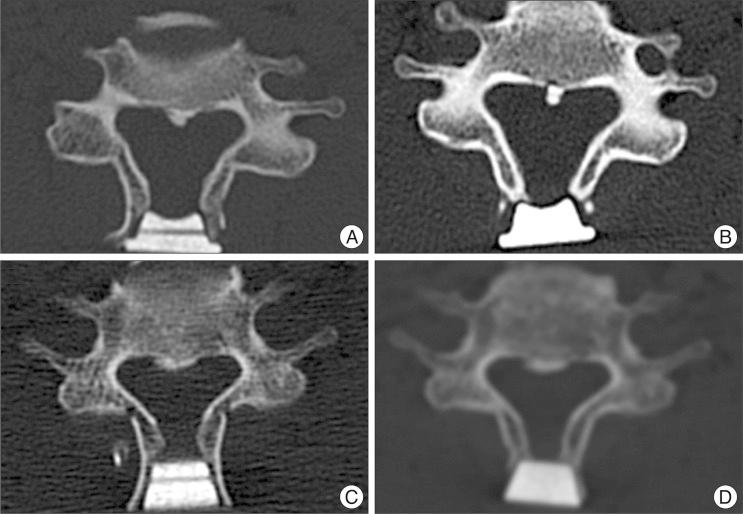

During January 2004 and January 2010, 45 patients with compressive cervical myelopathy underwent midline-splitting open door laminoplasty with winged (33 cases) and wingless (12 cases) HAs by a single surgeon. Minimal and mean follow up times were 12 and 28.1 months, respectively. Japanese Orthopedic Association (JOA) score was used for clinical outcome measurement. Cervical X-rays were taken preoperatively, immediately post-operatively, and after 3, 6, and 12 months and computed tomography scans were performed preoperatively, immediately post-operatively and after 12 months. Cervical lordosis, canal dimension, fusion between lamina and HA, and affecting factors of fusion were analyzed.

All surgeries were performed on 142 levels, 99 in the winged and 43 in the wingless HA groups. JOA scores of the winged group changed from 10.4±2.94 to 13.3±2.35 and scores of the wingless group changed from 10.8±2.87 to 13.8±3.05. There was no significant difference on lordotic and canal dimensional change between two groups. Post-operative 12 month fusion rate between lamina and HA was significantly lower in the winged group (18.2 vs. 48.8% p=0.001). Multivariate analysis showed that ossification of the posterior longitudinal ligament, male gender, and wingless type HA were significantly associated with fusion.

Clinical outcome was similar in patients receiving winged and wingless HA, but the wingless type was associated with a higher rate of fusion between HA and lamina at 12 months post-operatively.

方法

2004年1月至2010年1月期间,45例压迫性颈椎病患者由同一位外科医生采用带翼(33例)和无翼(12例)HA行中线劈开开门式椎板成形术。最短和平均随访时间分别为12个月和28.1个月。采用日本骨科协会(JOA)评分评估临床疗效。术前、术后即刻、术后3、6和12个月拍摄颈椎X线片,术前、术后即刻和术后12个月进行计算机断层扫描。分析颈椎前凸、椎管尺寸、椎板与HA之间的融合情况以及融合的影响因素。

结果

所有手术共涉及142个节段,带翼HA组99个节段,无翼HA组43个节段。带翼组JOA评分从10.4±2.94变为13.3±2.35,无翼组评分从10.8±2.87变为13.8±3.05。两组之间在颈椎前凸和椎管尺寸变化方面无显著差异。术后12个月时,带翼组椎板与HA之间的融合率显著低于无翼组(18.2%对48.8%,p = 0.001)。多因素分析显示,后纵韧带骨化、男性性别和无翼型HA与融合显著相关。

结论

接受带翼和无翼HA的患者临床疗效相似,但无翼型在术后12个月时HA与椎板之间的融合率更高。